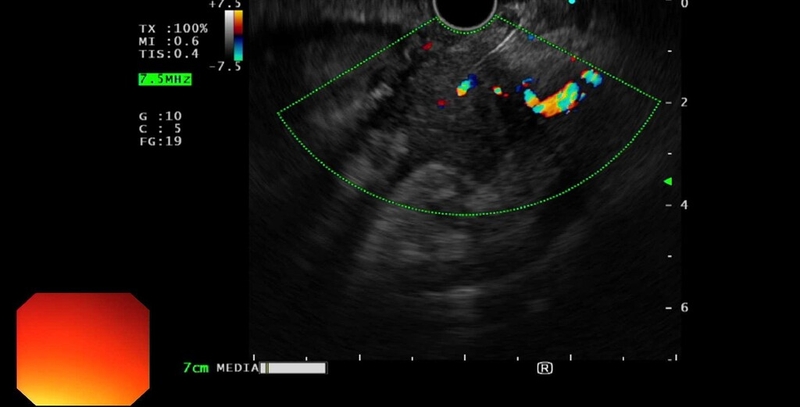

Nang giả tụy thường đặc trưng bởi tình trạng các vách hay các mảng lắng không đồng đều do tụy bị chảy máu hay mô bị hoại tử. Đồng thời, những thành phần tăng âm tồn tại bên trong tụy ngày một nhiều cũng tạo điều kiện cho vi khuẩn tấn công và gây nên tình trạng bội nhiễm. Do đó, để chẩn đoán nang giả tụy, bác sĩ sẽ chỉ định siêu âm tụy kết hợp siêu âm Doppler.